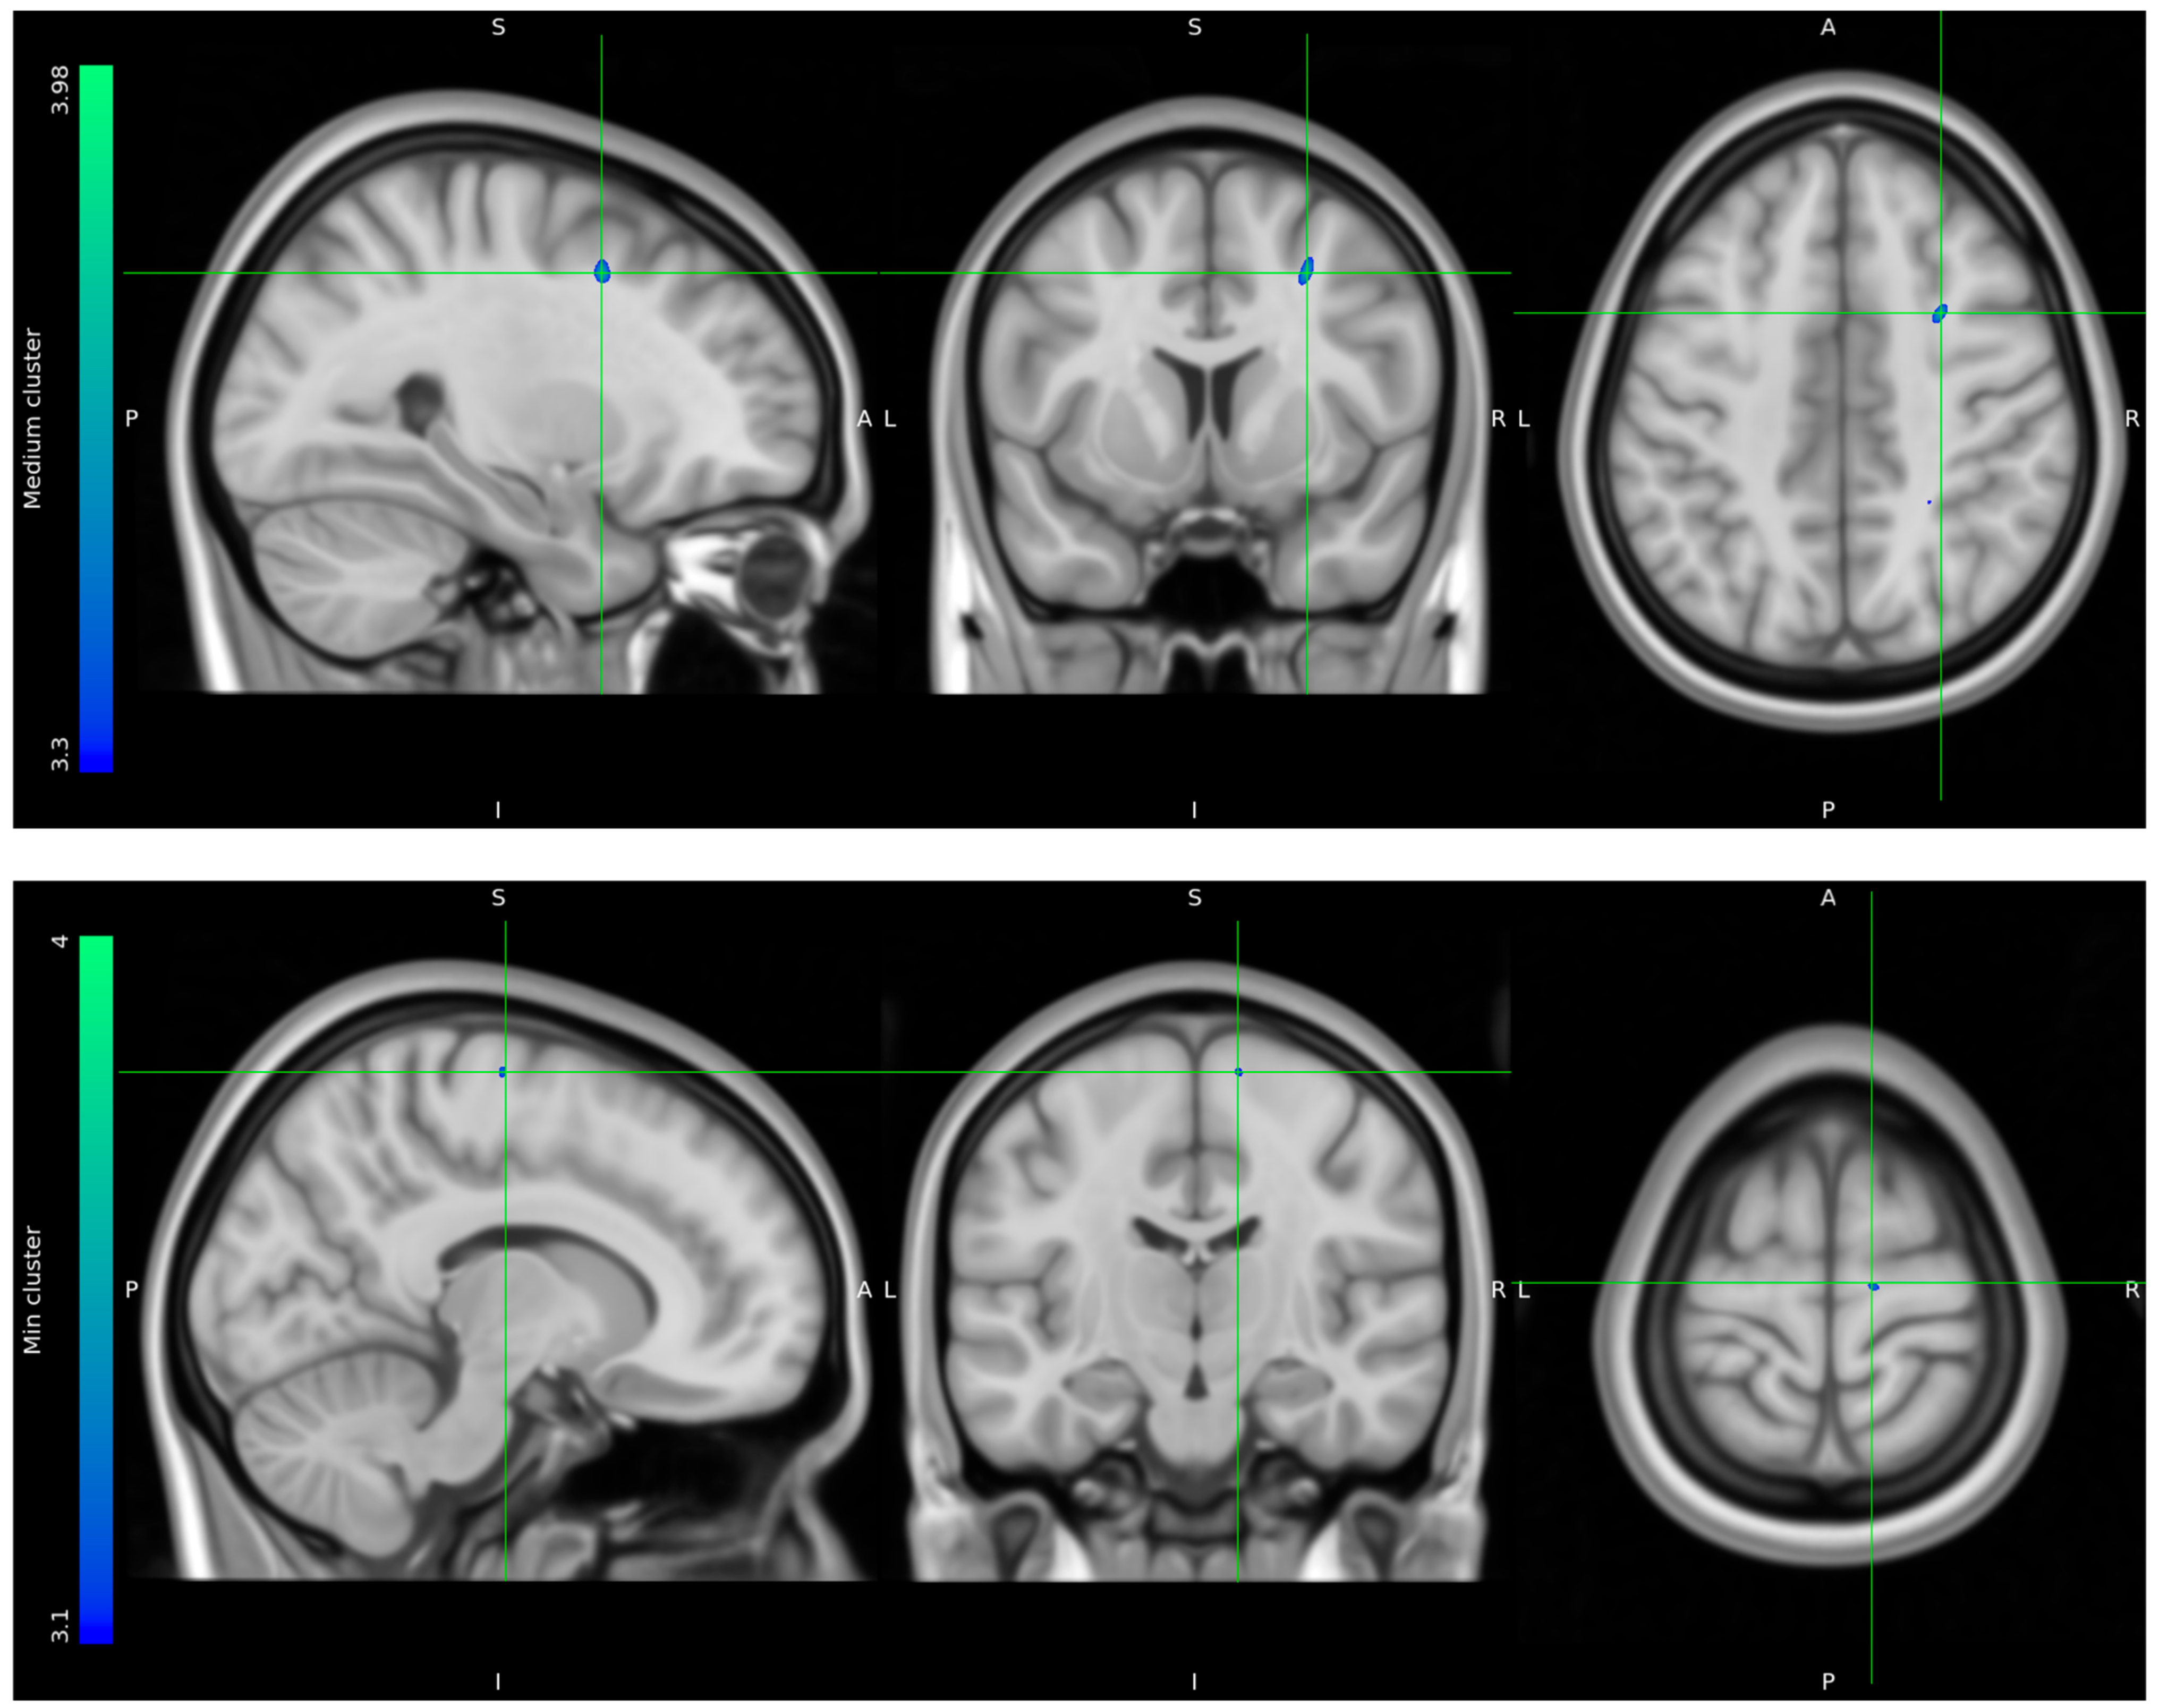

3.2. FDG-PET Brain Imaging Scans